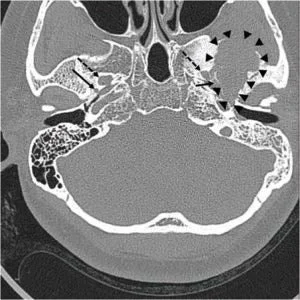

A pre-operative computed tomography (CT) scan, performed in preparation for planned Eustachian tube balloon dilatation, revealed an unexpected finding: a large, ill-defined osteolytic lesion with adjacent sclerotic changes in the left middle cranial fossa. Subsequent magnetic resonance imaging (MRI) provided a more detailed picture, identifying an approximately 4-cm heterogeneous mass. This tumor was located in the left temporal bone, involving the sphenoid bone and the left temporomandibular joint surface, with extension downwards into the infratemporal fossa. The MRI characteristics, including mixed signal intensities on T1-weighted images, markedly low signal on T2 imaging with cystic changes, and heterogeneous enhancement post-contrast, were highly suggestive of a giant cell tumor. Further investigation with positron emission tomography (PET) confirmed a strong uptake of 18F-fluoro-2-deoxy-D-glucose (18F-FDG), indicating metabolic activity consistent with a tumor in the infratemporal fossa. Crucially, imaging confirmed the tumor was adjacent to the foramen spinosum, the anatomical entry point for the MMA, but did not directly contact the foramen ovale.

The embolization technique involved accessing the patient’s vascular system via the right common femoral artery using a 5-French micropuncture kit. Standard angiography was performed to visualize the common carotid and external carotid arteries. Subsequently, a microcatheter was advanced to selectively catheterize the left accessory MMA. Utilizing a detachable coil, the MMA was then occluded. Post-embolization temporal bone CT scans confirmed the successful occlusion of the artery.